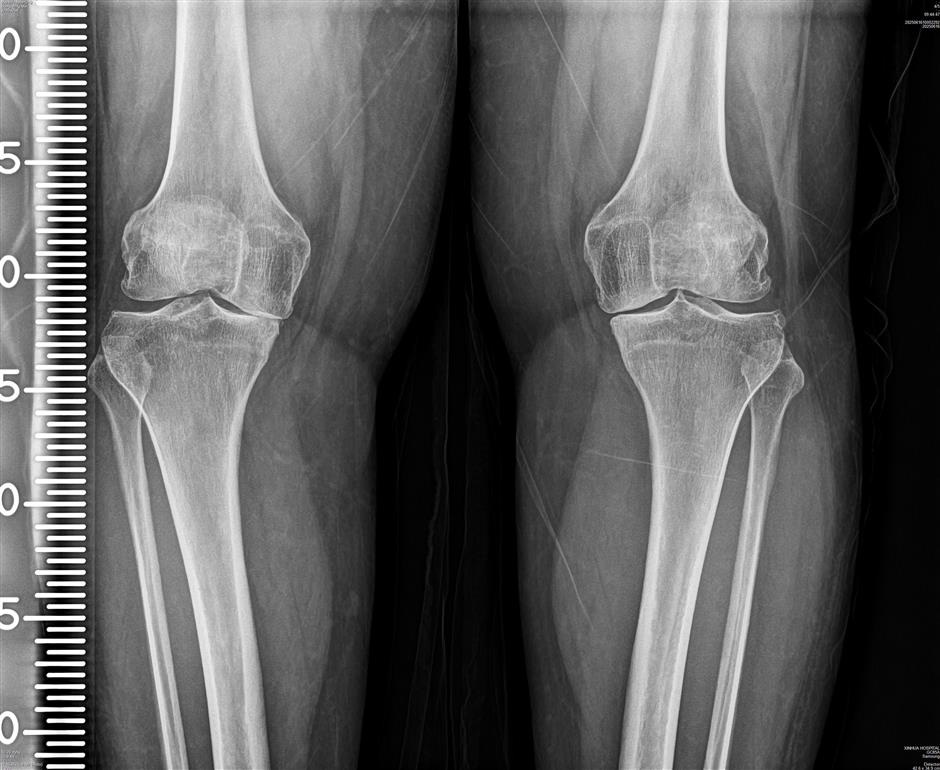

Researchers at Xinhua Hospital in Shanghai and in Singapore have developed a nano-delivery system that targets arthritis-affected cells, giving hope to 500 million arthritis patients worldwide.

Progressive arthritis degrades joint cartilage, causing pain, swelling, and mobility issues. Current treatments mostly alleviate symptoms but do not stop disease progression.